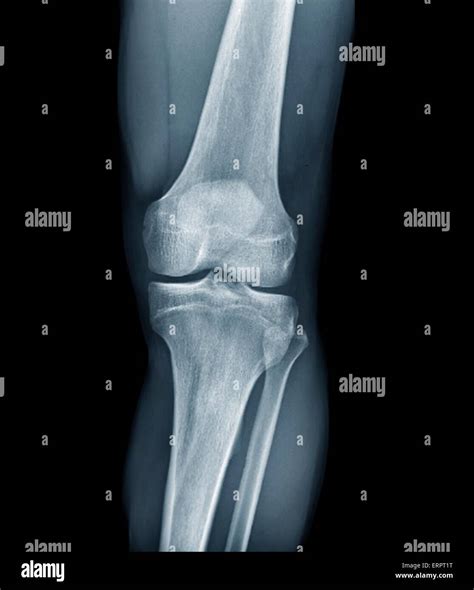

Understanding Knee X-rays

Knee X-rays are a type of medical imaging that uses low doses of radiation to produce images of the knee joint. These images help doctors identify various conditions, including fractures, dislocations, and degenerative changes. The process is non-invasive and relatively quick, making it a preferred method for initial knee evaluations.

Interpreting Healthy Knee X-rays

Interpreting knee X-rays requires a trained eye. Here are some key features that radiologists look for in Healthy Knee X-rays:

• Bone Structure: The bones of the knee, including the femur, tibia, and patella, should appear smooth and intact without any fractures or deformities.

• Joint Space: The space between the bones should be uniform and not narrowed, which can indicate wear and tear or arthritis.

• Soft Tissue: While X-rays primarily show bone, the soft tissue around the knee should appear normal without any signs of swelling or inflammation.

• Alignment: The knee joint should be properly aligned, with no signs of dislocation or misalignment.